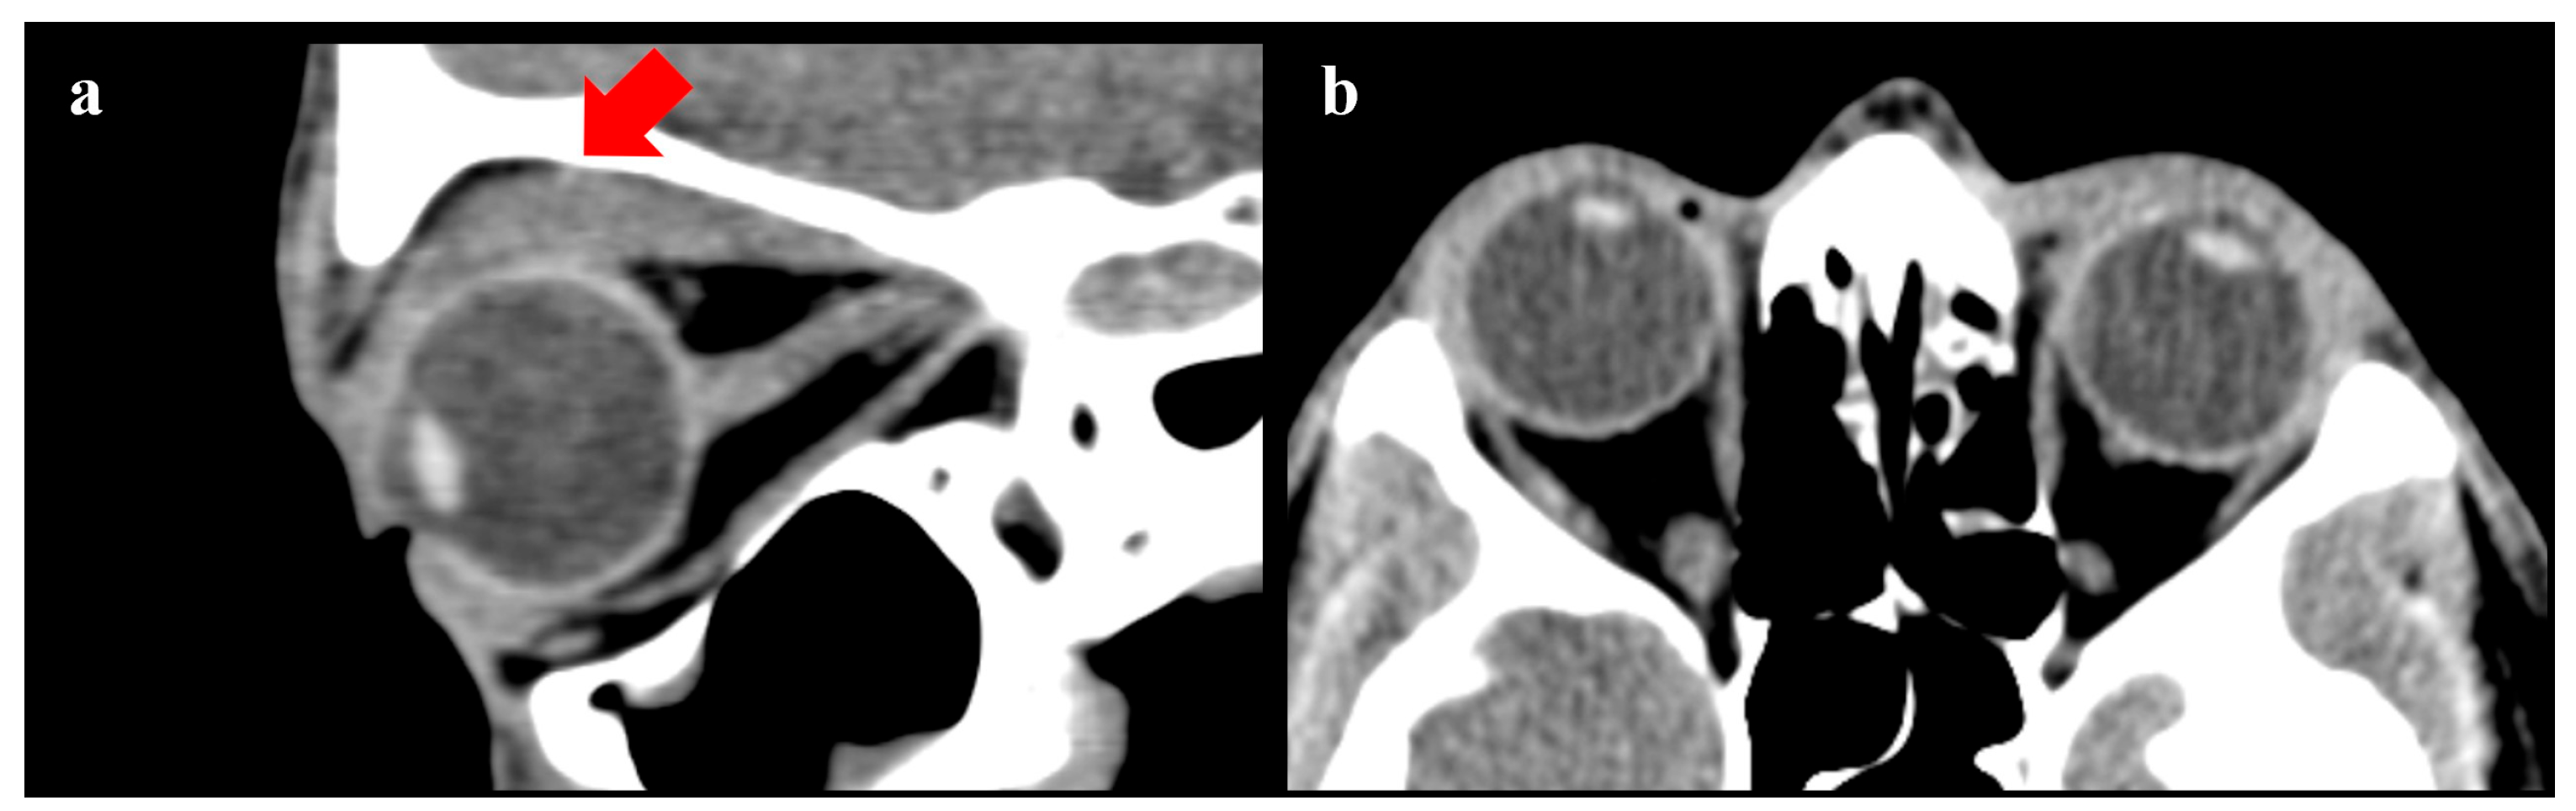

The surgical procedure lasted 1 h, and no complications were reported. After a short period of observation, the patient was discharged. In the first two months after the surgery, no anomalies of interest occurred (Figure 1). After this period, left lagophthalmos was reported and rapidly worsened (Figure 2). Five months after the procedure, a CT scan of the head was performed to find the cause of this adverse event. It showed regular orbital fat and eye muscles and, only in the left eye, thickened eyelids (Figure 3). In the following months, MRI scans were performed, finding a bilateral increase in the thickness of the eye muscles (Figure 4).

Figure 3.

CT scan performed 5 months after surgery. (a) Sagittal view—the LM/SR muscle complex increase is highlighted in red. (b) Coronal view.